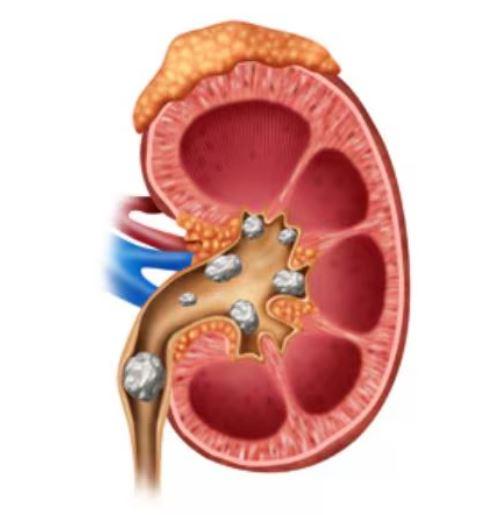

Best Kidney Stone Surgeon in Thane – Advanced Lase...

Kidney Stone Removal in Thane – Safe & Effective P...

Kidney Stone Removal Treatment in Siddharth Nagar,...

Top-Rated Kidney Stone Surgeon Near Me in Veer Sav...

Best Treatments for Kidney Stones at Our Clinic Ki...

Best Kidney Stone Treatment in Thane West – Non-Su...

Kidney Stone Pain in Thane – Advanced Treatment fo...

Exploring Advanced Urology Procedures in Thane Wes...